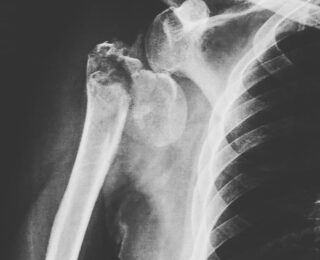

Paciente masculino de 69 años que presenta fractura de cabeza humeral y que inicialmente es tratado por «huesero» empíricamente, hasta que asiste con rayosX 20 días después de la fractura inicial.

Se le propone prótesis de hombro, con buenos resultados recuperando parcialmente arcos de movilidad y lo más importante: se encuentra sin dolor.